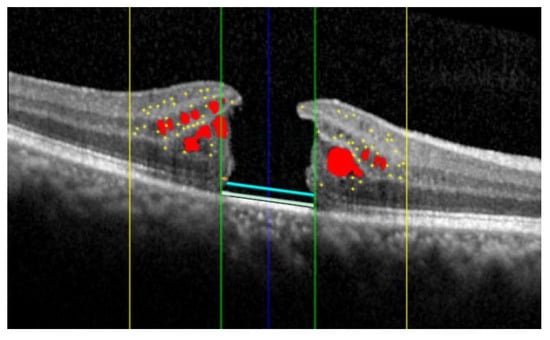

The AI algorithm allows for the simultaneous evaluation of several OCT biomarkers, as illustrated in Figure 1 and Figure 2.

Figure 1.

Summary of the distinct biomarkers assessed using Spectral Domain Optical Coherence Tomography (SD-OCT): intraretinal fluid (red); hyperreflective retinal foci (yellow dots) localized within the central 3 mm (yellow lines); interruption of the external limiting membrane (light blue) and ellipsoid zone (teal); the external limiting membrane (orange) and ellipsoid zone (yellow) localized within the central 1 mm (green lines).